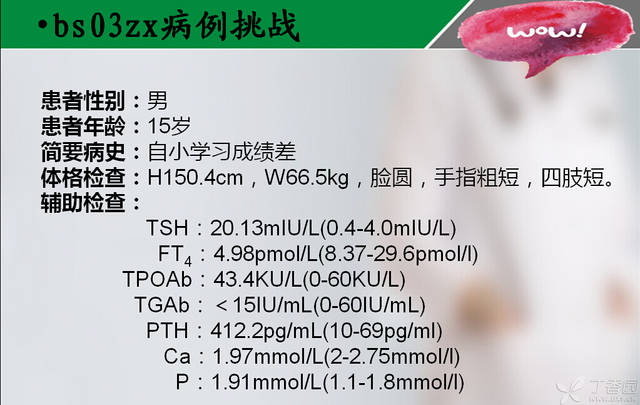

【bs03zx病例挑战】骨骼惊奇的少年,你能维护世界和平吗?

1.低钙、高磷、高PTH

2.典型AHO体征(身材矮小、肥胖、圆脸、第4掌骨/跖骨缩短、皮下钙化)

4.非自身免疫性的原发性甲减

PHP1A型患者的Gsα缺陷可能不仅与PTH抵抗有关,还可能存在对其他激素的抵抗,如TSH、胰高糖素及促性腺激素,导致甲状腺和性腺的功能减退。——《威廉姆斯内分泌学》